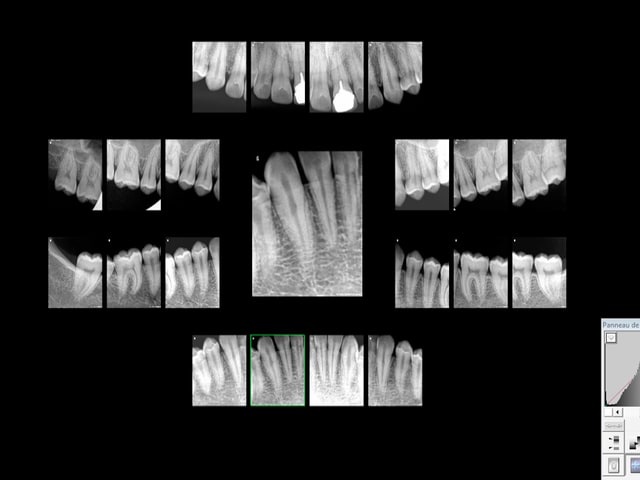

exemple :

justification : antécédent de soins intensifs, traitement orthodontique.

justification : signe d'appel antécédent de choc antérieur.

Doublement pas de bol le garçon pété une incisive qui a été traitée de façon comment dire ? étonnante !

Il est prévenu, il préfère attendre tranquillement sa pèche. A un de ces 4 ! -)))

Je suis sur que tu ne la fais meme pas la radio de l'incisive, me trompe je ? -)

A ma décharge le status n'est pas tout à fait complet il manque quelques apex. -)